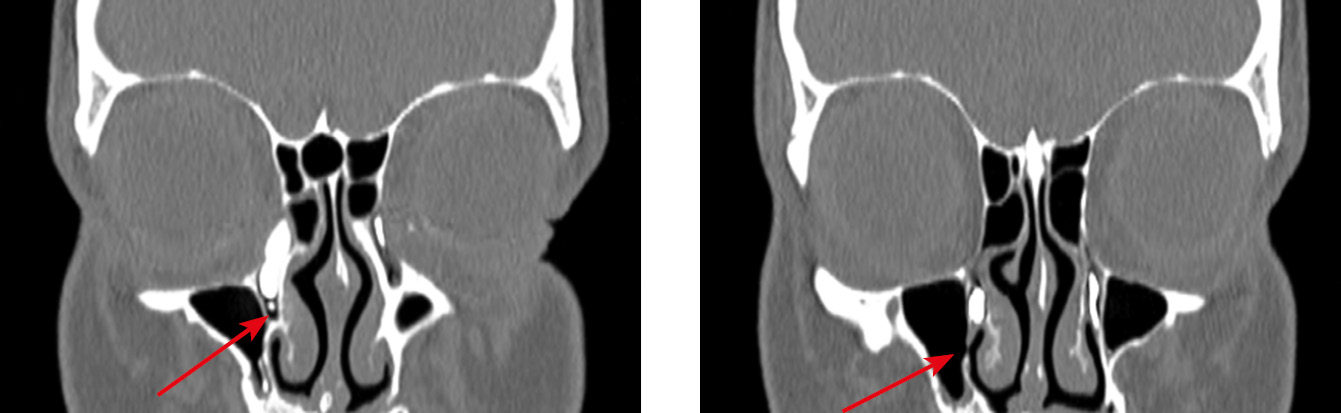

Интересен тот факт, что в двух случаях нашей серии нарушение проходимости СОП возникло после осуществления вмешательств на структурах наружного носа, а именно при проведении остеотомии в ходе ринопластики (рис. 8–10). По данным литературных источников, такие осложнения встречаются крайне редко, в основном при латеральной остеотомии [23, 24].

Рис. 8. Состояние после риносептопластики. Саккальная непроходимость слезоотводящих путей слева после проведения латеральной остеотомии (стрелки)

Fig. 8. Status post rhinoseptoplasty. Left lacrimal duct obstruction after lateral osteotomy (arrows)

Рис. 9. Двустороннее нарушение проходимости вертикального отдела слезоотводящих путей; слева — после проведения латеральной остеотомии на уровне верхней трети носослезного канала (постсаккальная непроходимость)

Fig. 9. Bilateral obstruction of the vertical part of the lacrimal ducts; on the left, status post lateral osteotomy at the level of the upper third of the nasolacrimal canal (post-saccal obstruction)